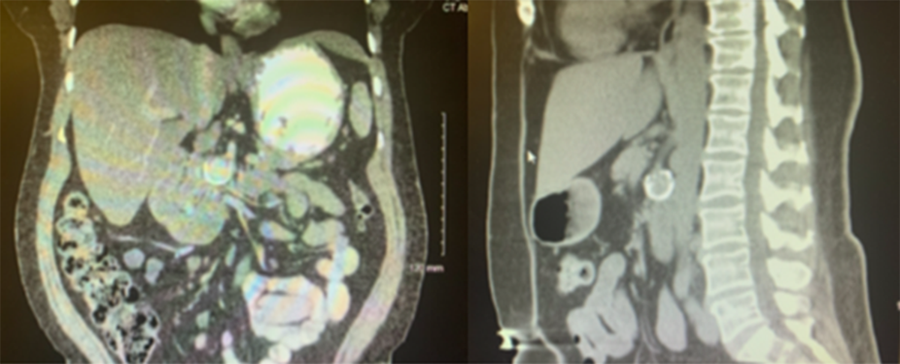

The patient is a 55-year-old female with a history of anxiety, GERD, hiatal hernia, hypertension, pancreatitis, tobacco abuse, and remote blunt abdominal trauma who presented to a chiropractor for progressive back pain. Anteroposterior and lateral lumbar films revealed a hyper-enhancing mass in the left upper quadrant. Spinal manipulation was aborted. Additional imaging revealed a peripherally calcified lesion measuring 2.4 cm that the radiologist deemed suggestive of a pseudoaneurysm of the SMA (Figure 1).

Figure 1. Pseudoaneurysm off Superior Mesenteric Artery. Published With Permission